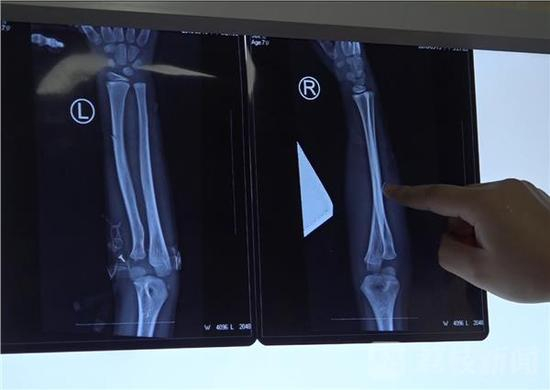

据 孩子的四爷爷介绍,男童叫小坤,今年7岁,孩子的父亲在外打工,由于平日继母对孩子就不好,孩子的父亲就将孩子放在他家里抚养。没想到在中秋节当天早上, 孩子的继母竟然对孩子痛下毒手。据徐州仁慈医院手足显微外科副主任齐伟亚介绍,孩子全身共有20多处刀伤,双手手臂被刀砍骨折,孩子的头部也有多处致命 伤,其入院时伤势非常严重。